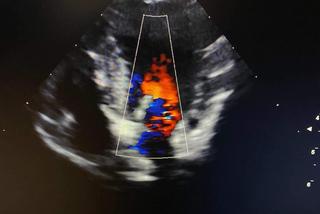

W wywiadzie doprecyzowano, że Tofikowi w codziennych czynnościach towarzyszy uporczywy kaszel oraz nietolerancja wysiłkowa. Podczas osłuchiwania serca stwierdzono szmer! Stanowi on bezwzględne wskazanie do skierowania czworonożnego pacjenta na badanie echokardiograficzne serca. Tak też stało się w przypadku Tofika.

Podczas wykonywania badania echokardiograficznego, stwierdzono u Tofika zastoinową niewydolność mięśnia sercowego, wynikającą z niedomykalności i zwyrodnienia zarówno zastawki mitralnej jak i trójdzielnej. Wyjaśnia to również, dlaczego Tofik ostatnio przybiera na masie, a jego brzuch staje się nabrzmiały. W wyniku niewydolności prawostronnej serca rozwinęło się wodobrzusze. Zmiany w sercu Tofika są najprawdopodobniej związane z wiekiem. Szybka reakcja właścicieli, trafna diagnoza oraz dobór prawidłowego leczenia sprawiły, że po tygodniu od momentu postawienia diagnozy oraz wdrożenia odpowiedniego leczenia kardiologicznego kaszel niemal całkowicie ustał, po obecności płynu w brzuchu nie ma śladu, a sam Tofik zmienił się nie do poznania, ma więcej siły i radości w sobie!